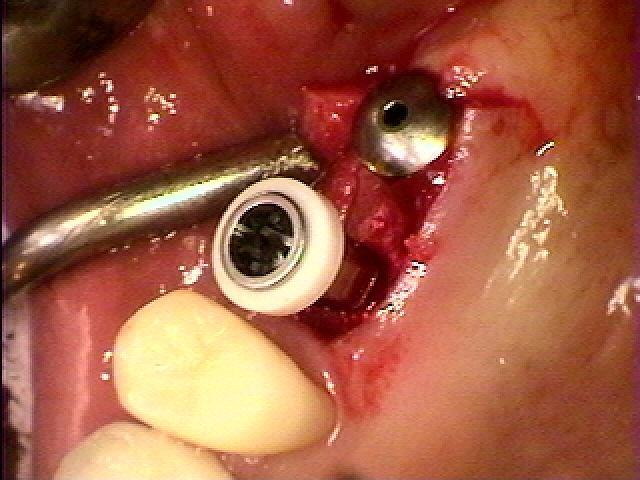

左上の6,7番部のインプラント埋入 38歳女性|お知らせ |広島市安佐南区の歯科医院 左上の6,7番部のインプラント埋入 38歳女性 トップ お知らせ・ブログ お知らせ 左上の6,7番部のインプラント埋入 38歳女性 左上の6,7番部のインプラント埋入 38歳女性 抜歯より1年が経ち傷もよくいえていました 歯茎を最小限で開けていきました インプラント埋入をおこなっています 2本埋入 骨の中にしっかりと入っています 縫合して終了となります 3か月待っています 印象を行い、カスタムのチタン製のアバットメントを建てていきました ジルコニアクラウンを作製していきました 綺麗に仕上がっています Web診療予約 初めての方へ 選ばれ続ける理由 院内設備について 歯が痛いしみる一般歯科 歯がぐらぐらする歯周病 健康な歯を保ちたい予防歯科 子供の虫歯予防をしたい小児歯科 銀歯をセラミックに審美歯科 白い歯を目指しませんか?ホワイトニング 矯正専門医がいるので安心矯正歯科 抜けた歯を補いたいインプラント・入れ歯 医院案内 スタッフ紹介 メリィハウス歯科クリニックオフィシャルホームページ ラベンダー歯科クリニックオフィシャルホームページ お知らせ・ブログ ホーム 診療科目 一般歯科 歯周病治療 予防治療 小児歯科 審美治療 ホワイトニング 矯正歯科 入れ歯・インプラント マウスピース矯正 初めての方へ 院長・スタッフ 設備紹介 医院案内・アクセス メニューを閉じる